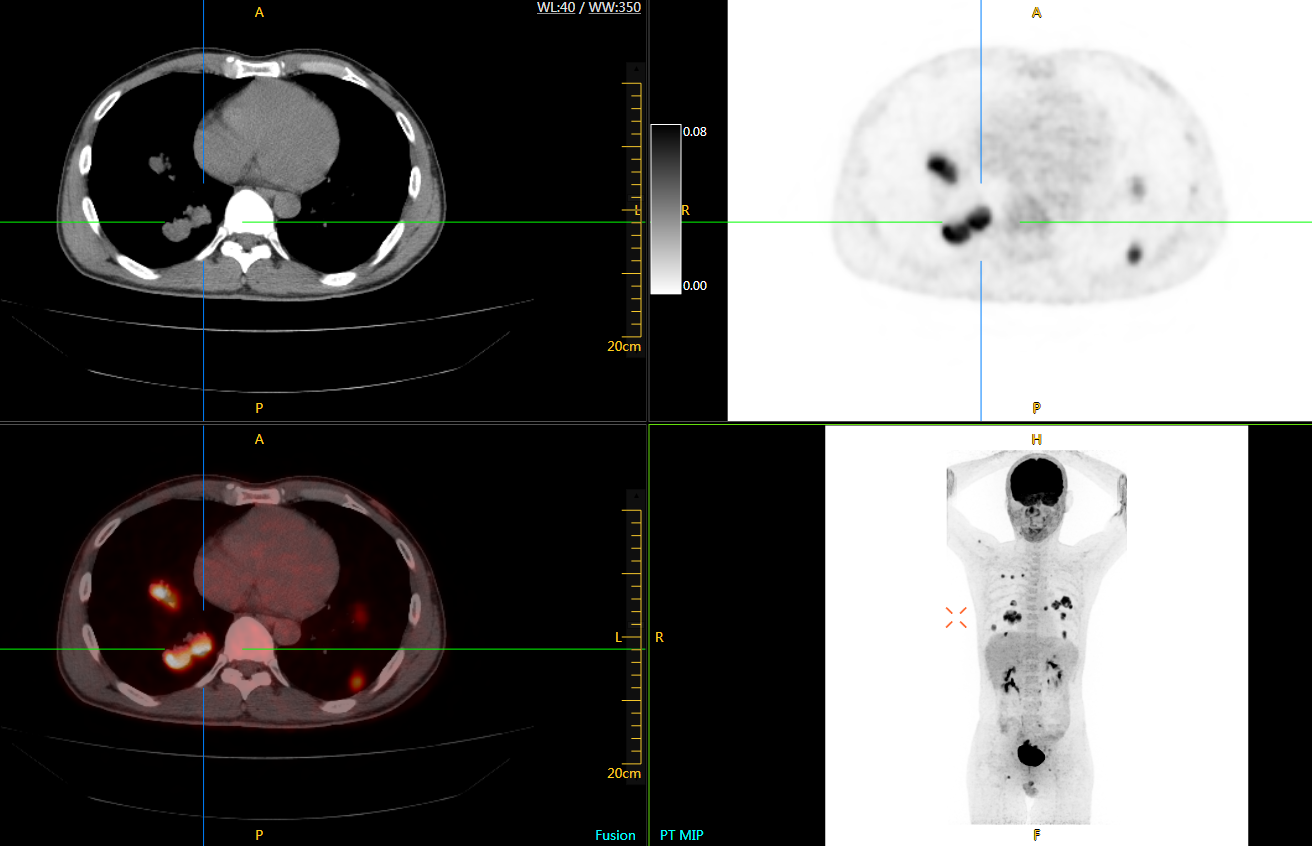

uExplorer探索者不再局限于傳統(tǒng)靜態(tài)代謝過程3D成像,而是在此基礎(chǔ)上新增一個維度——時(shí)間,從而實(shí)現(xiàn)4D全景成像。

注射總劑量為7.8mCi,14分鐘全身采集時(shí)間,在擁有超高靈敏度與超高分辨率的uEXPLORER上,即可得到展示顯示人體諸多精細(xì)結(jié)構(gòu)的高清三維圖像。

注射總劑量為7.8mCi,注射后1.6小時(shí),基于uEXPLORER探索者掃描1分鐘的圖像

注射總劑量為0.67 mCi FDG(低于常規(guī)劑量的十分之一),基于uEXPLORER探索者掃描15分鐘的圖像

注射總劑量為6.9mCi,注射后10小時(shí),基于uEXPLORER探索者掃描14分鐘的圖像